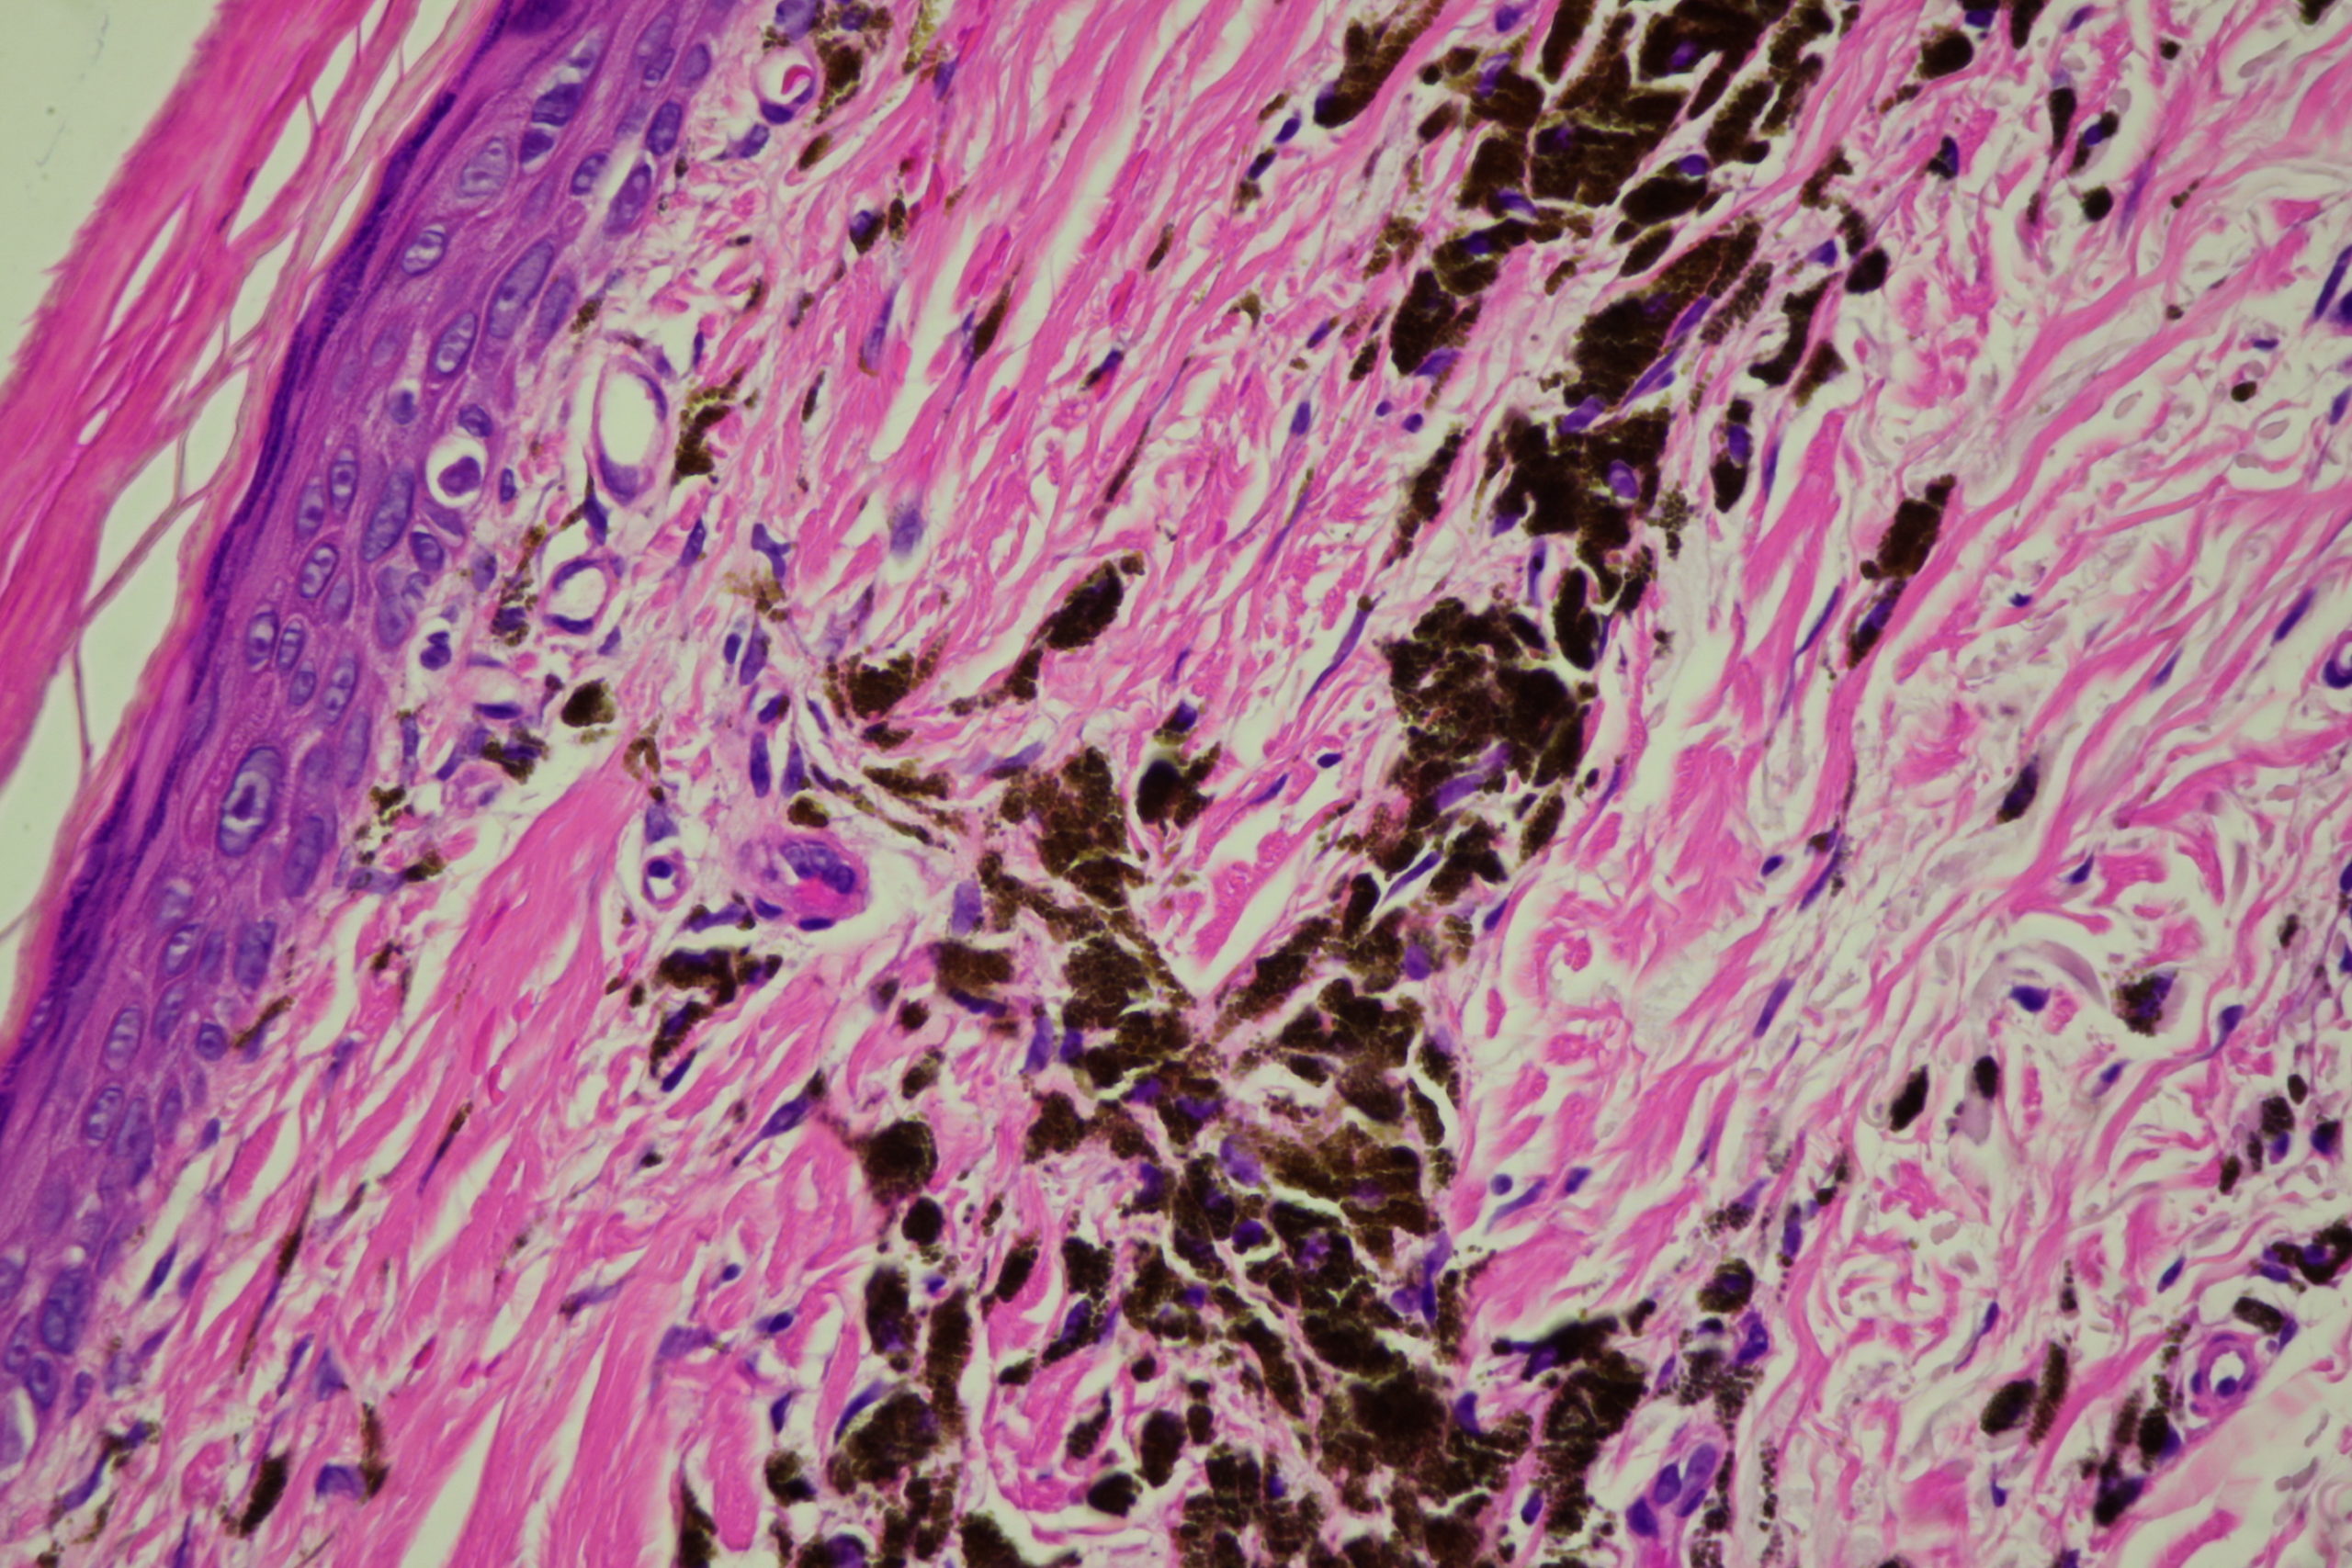

Diagnosis: Post Inflammatory Hyperpigmentation

Description: Note the perilesional hypopigmentation

These lesions arose after he went on Check Point inhibitor for metastatic melanoma. Note the perilesional hypopigmentation as well as the post inflammatory hyperpigmentation which was all that was left of his melanoma metastases. These had been stable for the last 9 months with no evidence in PET scans of melanoma elsewhere. This rteally shows the effectiveness of these immune stimulating drugs in metastatic melanoma.